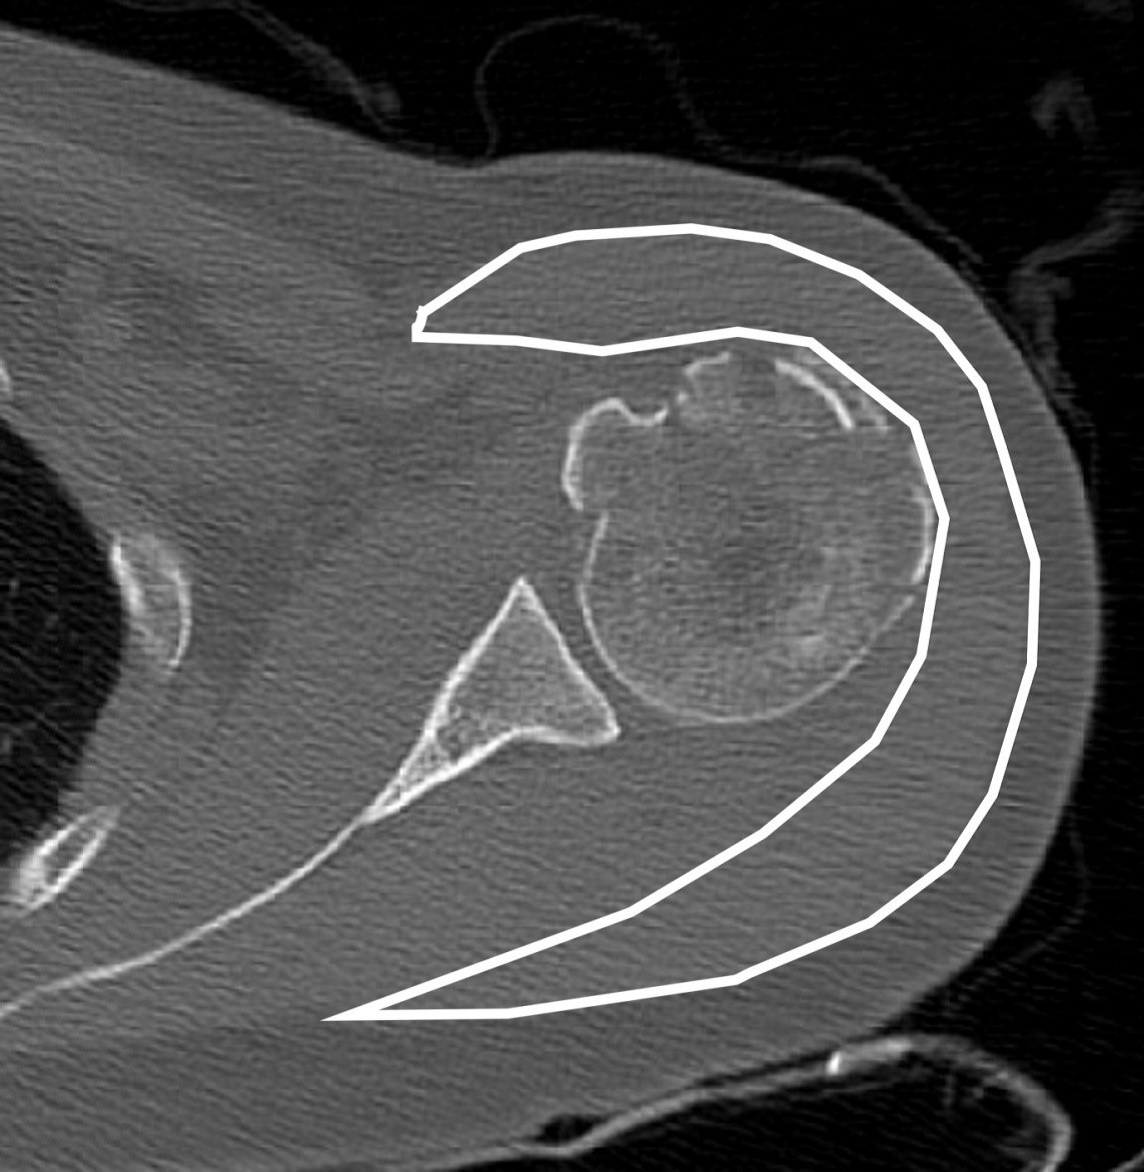

For the deltoid muscle volume evaluation, preoperative and l-year postoperative shoulder CT images were used. The deltoid muscle cross-sectional area was measured using axial CT at three positions: the upper edge area, lower edge area, and middle of the glenoid (Figure 4) [10,12]. The mean value of the three positions was calculated for deltoid muscle volume evaluation, and the ratio of the deltoid muscle volume was calculated using the following formula:

Ratio of deltoid volume = 100 × 1 year after deltoid volume/preoperative deltoid volume.

Figure 4: For deltoid muscle volume evaluation, the deltoid muscle cross-section was measured on axial computed tomography.